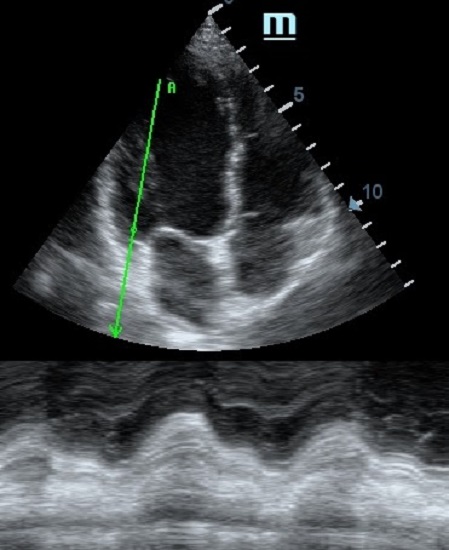

MAPSE - амплитуда движения латерального кольца митрального клапана, позволяет рассчитать фракцию выброса по формуле EF = 4.8 × MAPSE (mm) + 5.8, очень быстрый и гораздо более точный («прародитель Strain») метод чем широко распространенный метод Teicholtz. В современных приборах можно легко добавить свою формулу при отсутствии ее в стандартном калькуляторе. Главным условием является проведение линии М-режима параллельно стенке левого желудочка в апикальном четырехкамерном сечении, что легко достигается при использовании функции Free Xros.